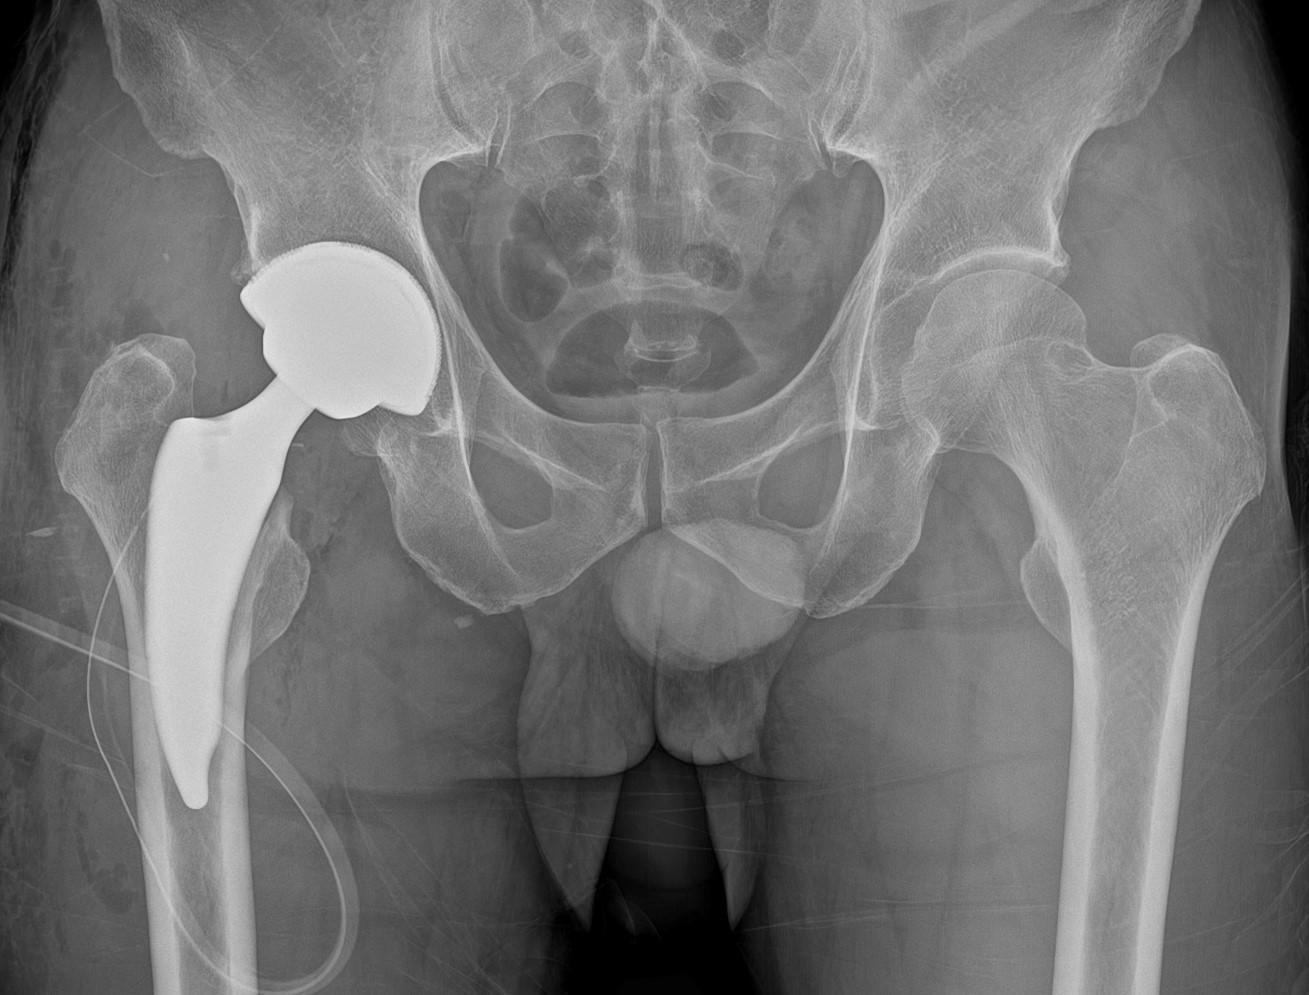

고관절 인공관절술 (치환술)

고관절 인공관절술 (치환술)은 외상 및 다양한 질환에 의해 고관절이 손상되어 보행이 어려운 환자에게, 손상된 관절을 재건하여 원활한 환자의 보행을 가능케 하는 수술입니다. 1950년경부터 시작된 현대 인공관절은, 정형외과 내에서도 그 역사가 가장 오래된 수술 중 하나로, 다른 어떤 정형외과 수술보다도 만족스러운 결과를 보고하고 있습니다.

손상된 관절 대신 인공관절을 삽입하여 통증을 완화해주고 경직된 운동범위를 확보하는 고관절 인공관절은 주로 관절염, 대퇴골두 무혈성 괴사, 고관절 골절 등에서 시행될 수 있습니다.

직접 전방 도달법 (Direct Anterior Approach) 을 통한 최소 침습 인공관절술

중앙대학교병원에서는 고관절 인공관절 술식에 있어 최근 세계적으로 주목받고 있는 수술법 중 하나인 직접 전방 도달법 (Direct Anterior Approach) 을 활발히 시행하고 있습니다.

고관절 인공관절치환술 직접전방도달법이란 고관절 인공관절치환술을 시행하는 환자에 대해 둔부쪽 근육을 절개하는 대신 고관절 앞쪽, 즉 전방 근육사이로 접근하는 방식으로, 기존에 주로 이용되던 후방접근법과 달리 근육을 절개하지 않고 근육 사이로 접근하기 때문에 인공관절의 탈구율이 현저하게 낮으며 수술 후 회복에 있어서도 수술 다음날부터 바로 보행이 가능하여, 기존 수술법보다 훨씬 빠른 기능 회복이라는 장점이 있습니다.

최소절개 인공관절술

위에서 소개한 고관절 인공관절치환술 직접전방도달법 외에도, 기존의 절개법과 비교하여 최소 절개를 기본으로 한 환자 개개인에 특성에 맞춘 인공관절 술식을 적용하고 있으며 이를 통해 수술로 인한 감염 위험을 최소화하고 빠른 회복을 통한 입원기간 단축을 목표로 하고 있습니다.